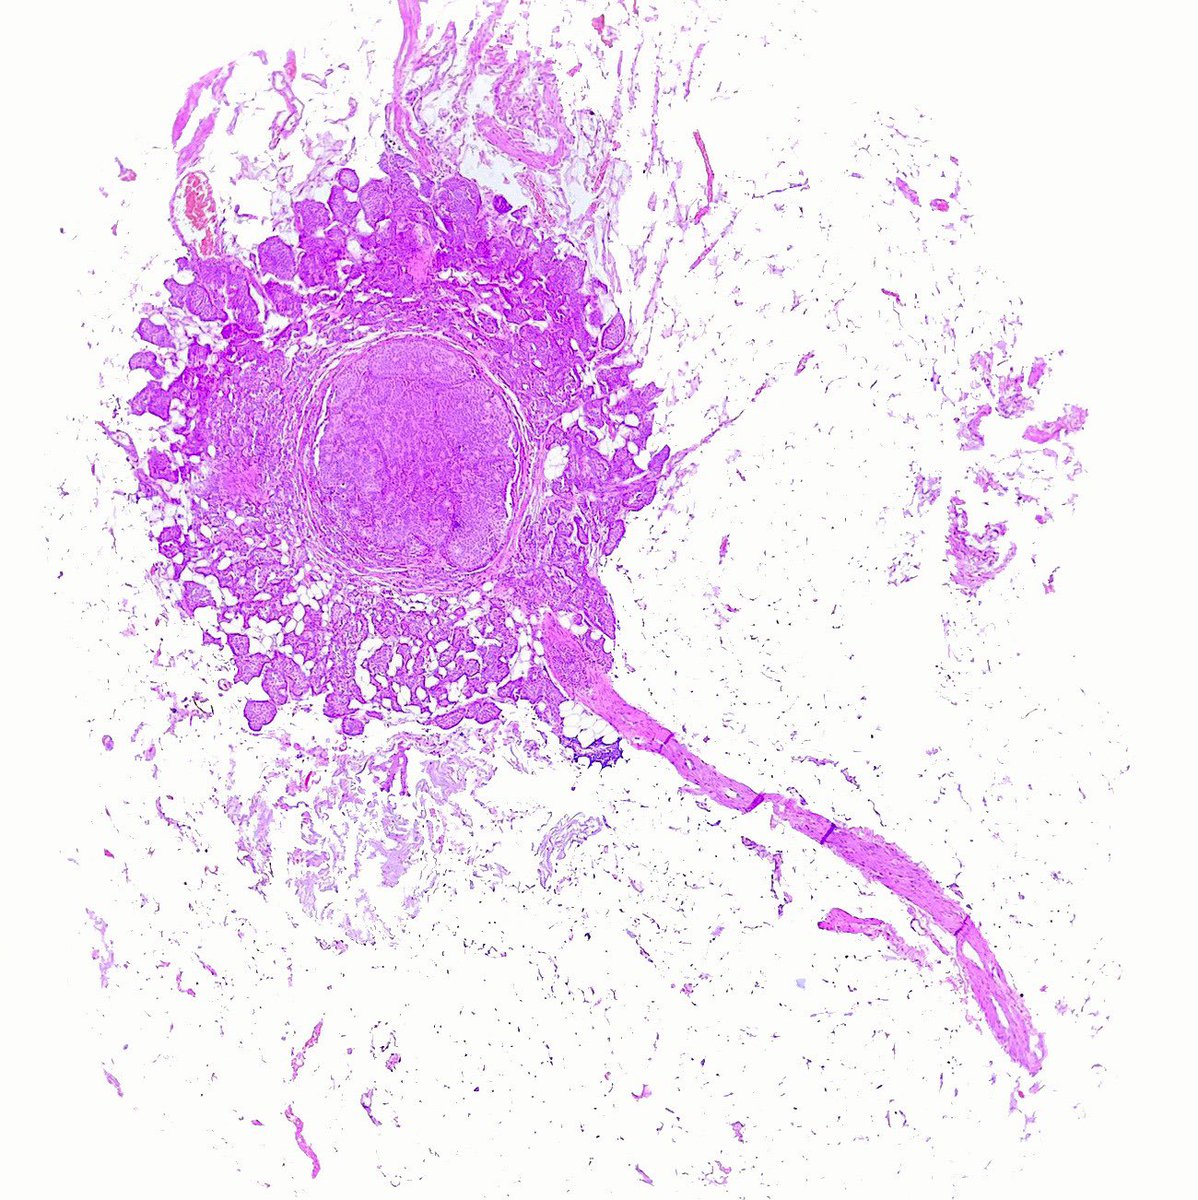

The frozen section